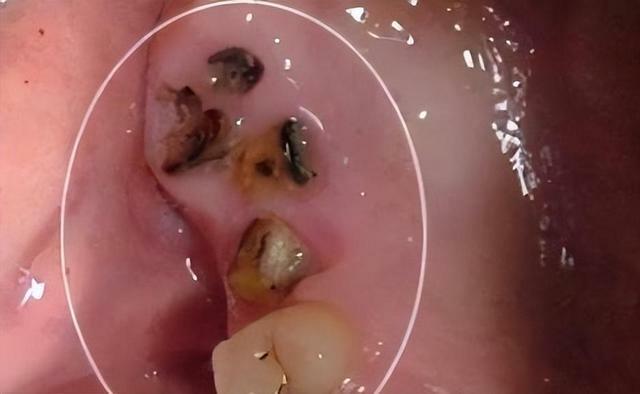

1、嚴重的齲齒

齲齒,俗稱蛀牙,是在以細菌為主的多種因素影響下,造成牙體組織發生慢性進行性破壞的一種疾病。

嚴重的齲齒會誘發牙髓炎、根尖炎,讓患者感到明顯的疼痛,如果放任根尖炎進一步發展,齲齒的細菌就會腐蝕掉牙齒正常形態。

如果牙齒被大面積破壞了,只留下殘根或小面積殘冠,不僅不能行駛正常的功能,殘根殘冠尖銳不規則的外形還可能會劃破口腔黏膜,造成口腔潰瘍反覆發作,甚至引發癌變。

因此,齲齒造成的殘根殘冠,若經醫生評估已無保留修復的必要,應儘早拔除。